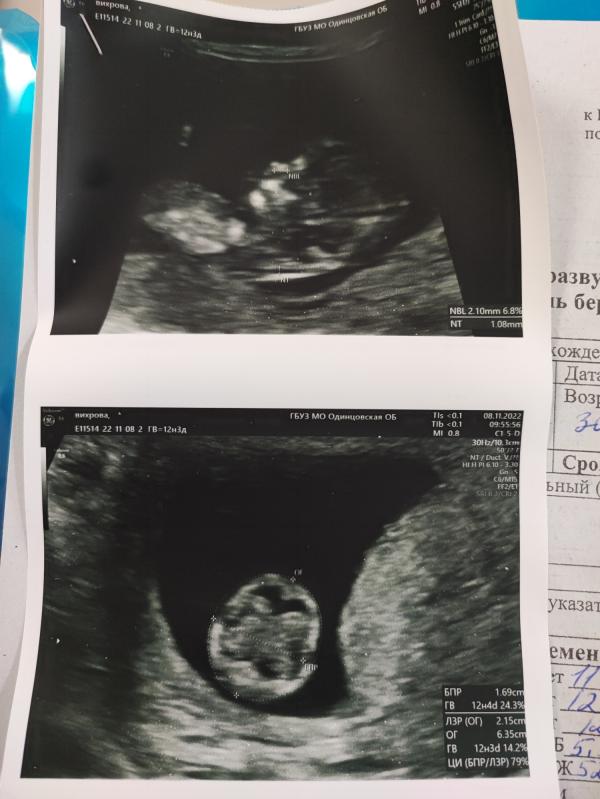

Мы прошли 1й скрининг ❤️ я настолько счастлива, что на УЗИ прослезилась) Все хорошо. Ручки, ножки, носик, пальчики - все на месте) пальчики даже посчитали с врачом, такая милота. Ну как не прослезиться 🥺

Только нам сказали, что мы маленькие. Срок поставили 11,6 вместо 12,3. Но сказали, что не критично. Очень верю в это 🙏

В целом я приятно удивлена) приняли меня на час раньше. Я ездила еще к стоматологу. От него сразу пошла на УЗИ и села ждать около кабинета. Врач узист все подробно показала и р...